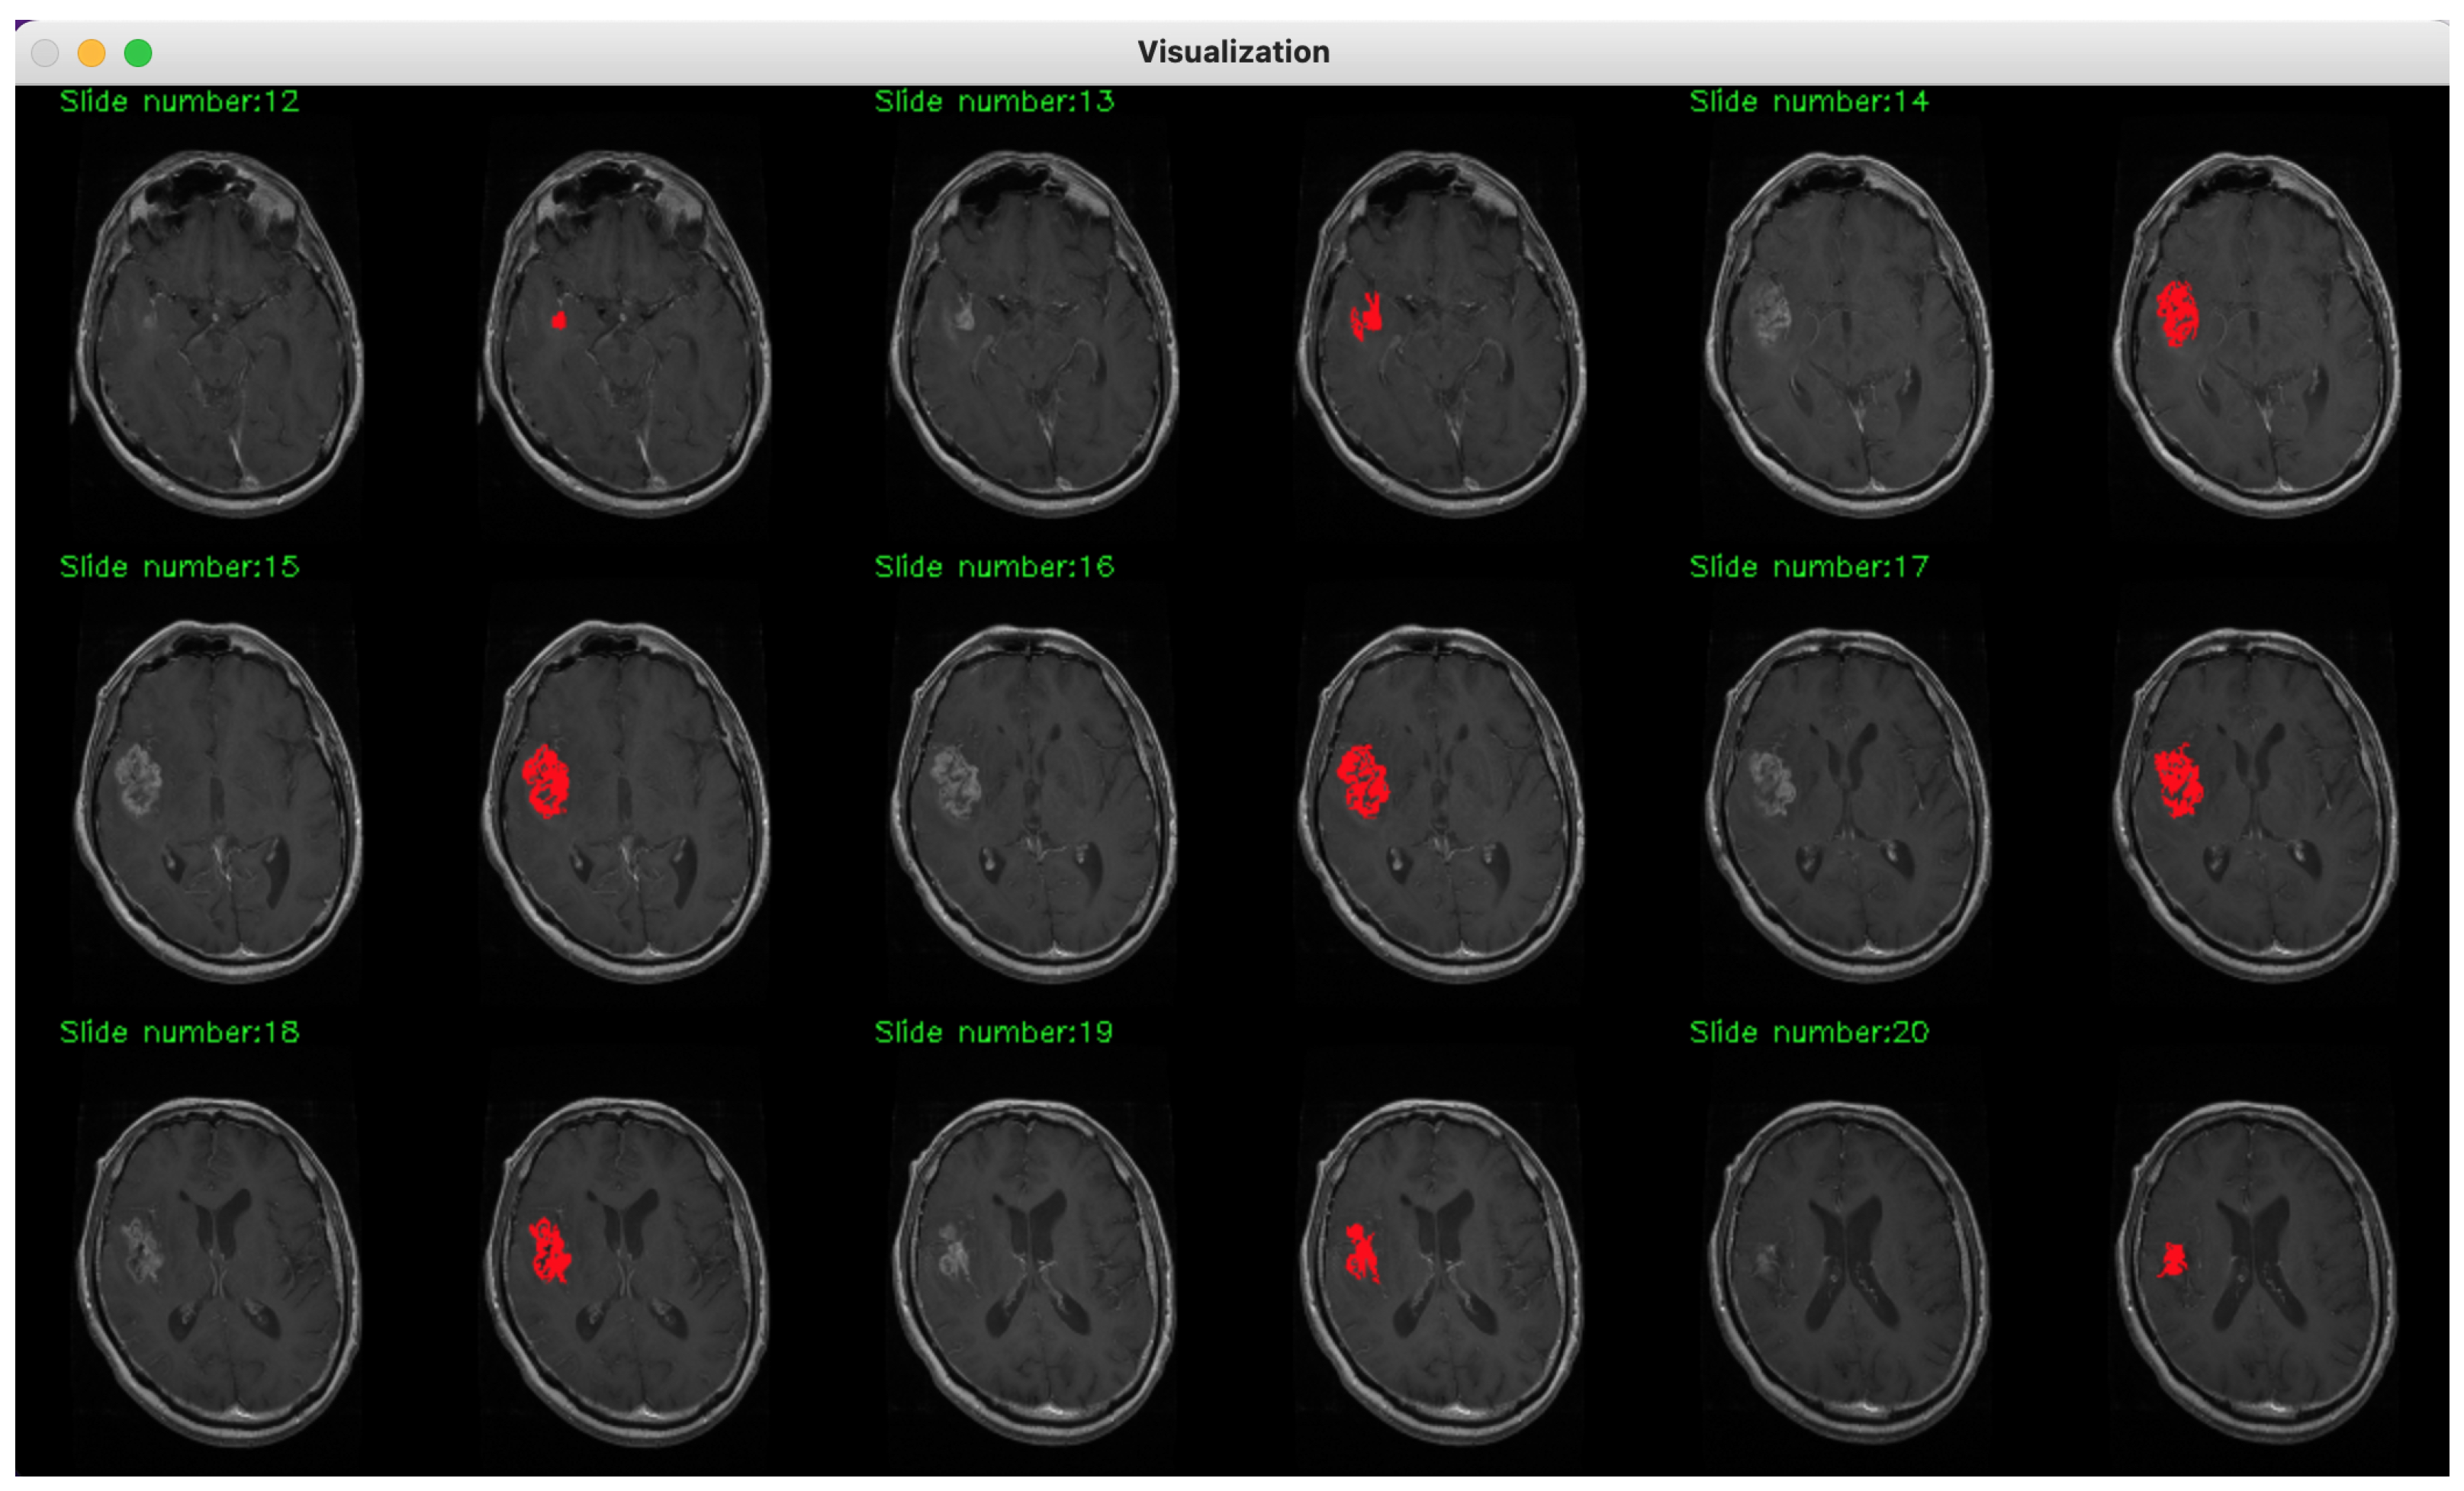

2. Method Description